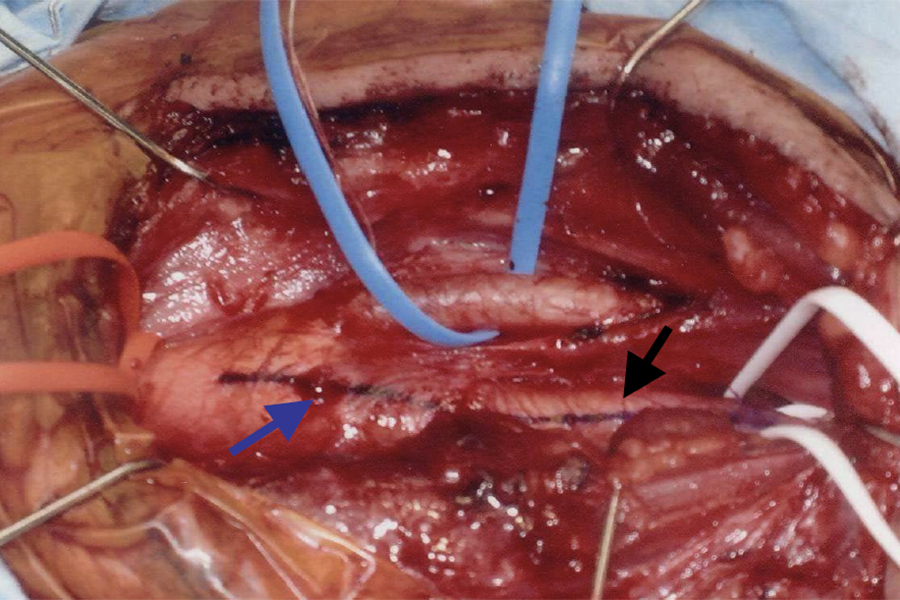

手術方法

全身麻酔で行います。

- 頚部を切開し、頚動脈を露出します。

- 動脈を切開します。

- 狭窄の原因であるプラークを直接取り除きます。

- 動脈を縫合し、血流を改善させます。

血管を直接きれいにする、確立された標準的治療です。